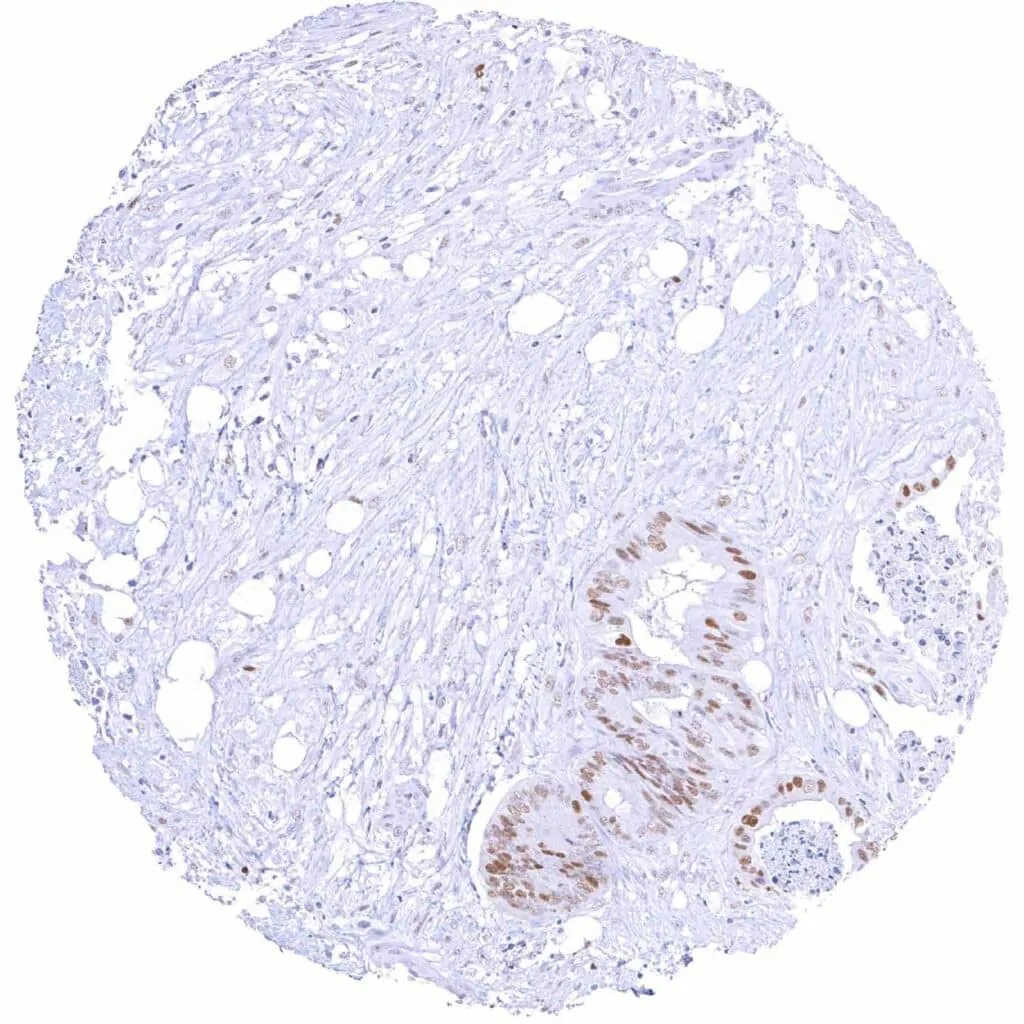

Colon – Colorectal adenocarcinoma with mucinous features and a moderate to strong Cyclin E1 staining of only very few tumor cells